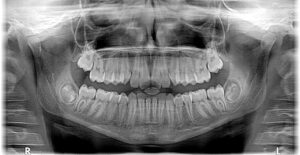

Consultation & CBCT

Assess candidacy and plan your smile.

A 3D CBCT scan helps us evaluate bone levels, review goals, and outline treatment options.

World-Class Imaging and Scanning

We use the latest intraoral scanners including Trios 5, iTero Lumina, and Emerald S, along with the Micron Mapper for photogrammetry. A Kavo OP 3D CBCT and Dexis Titanium sensors provide ultra-detailed 3D imaging.

Advanced Imaging and Scanning

We use the latest intraoral scanners, including Trios 5, iTero Lumina, and Emerald S, along with Micron Mapper for photogrammetry. Our Kavo OP 3D CBCT and Dexis Titanium sensors deliver clear, detailed imaging for surgical planning.